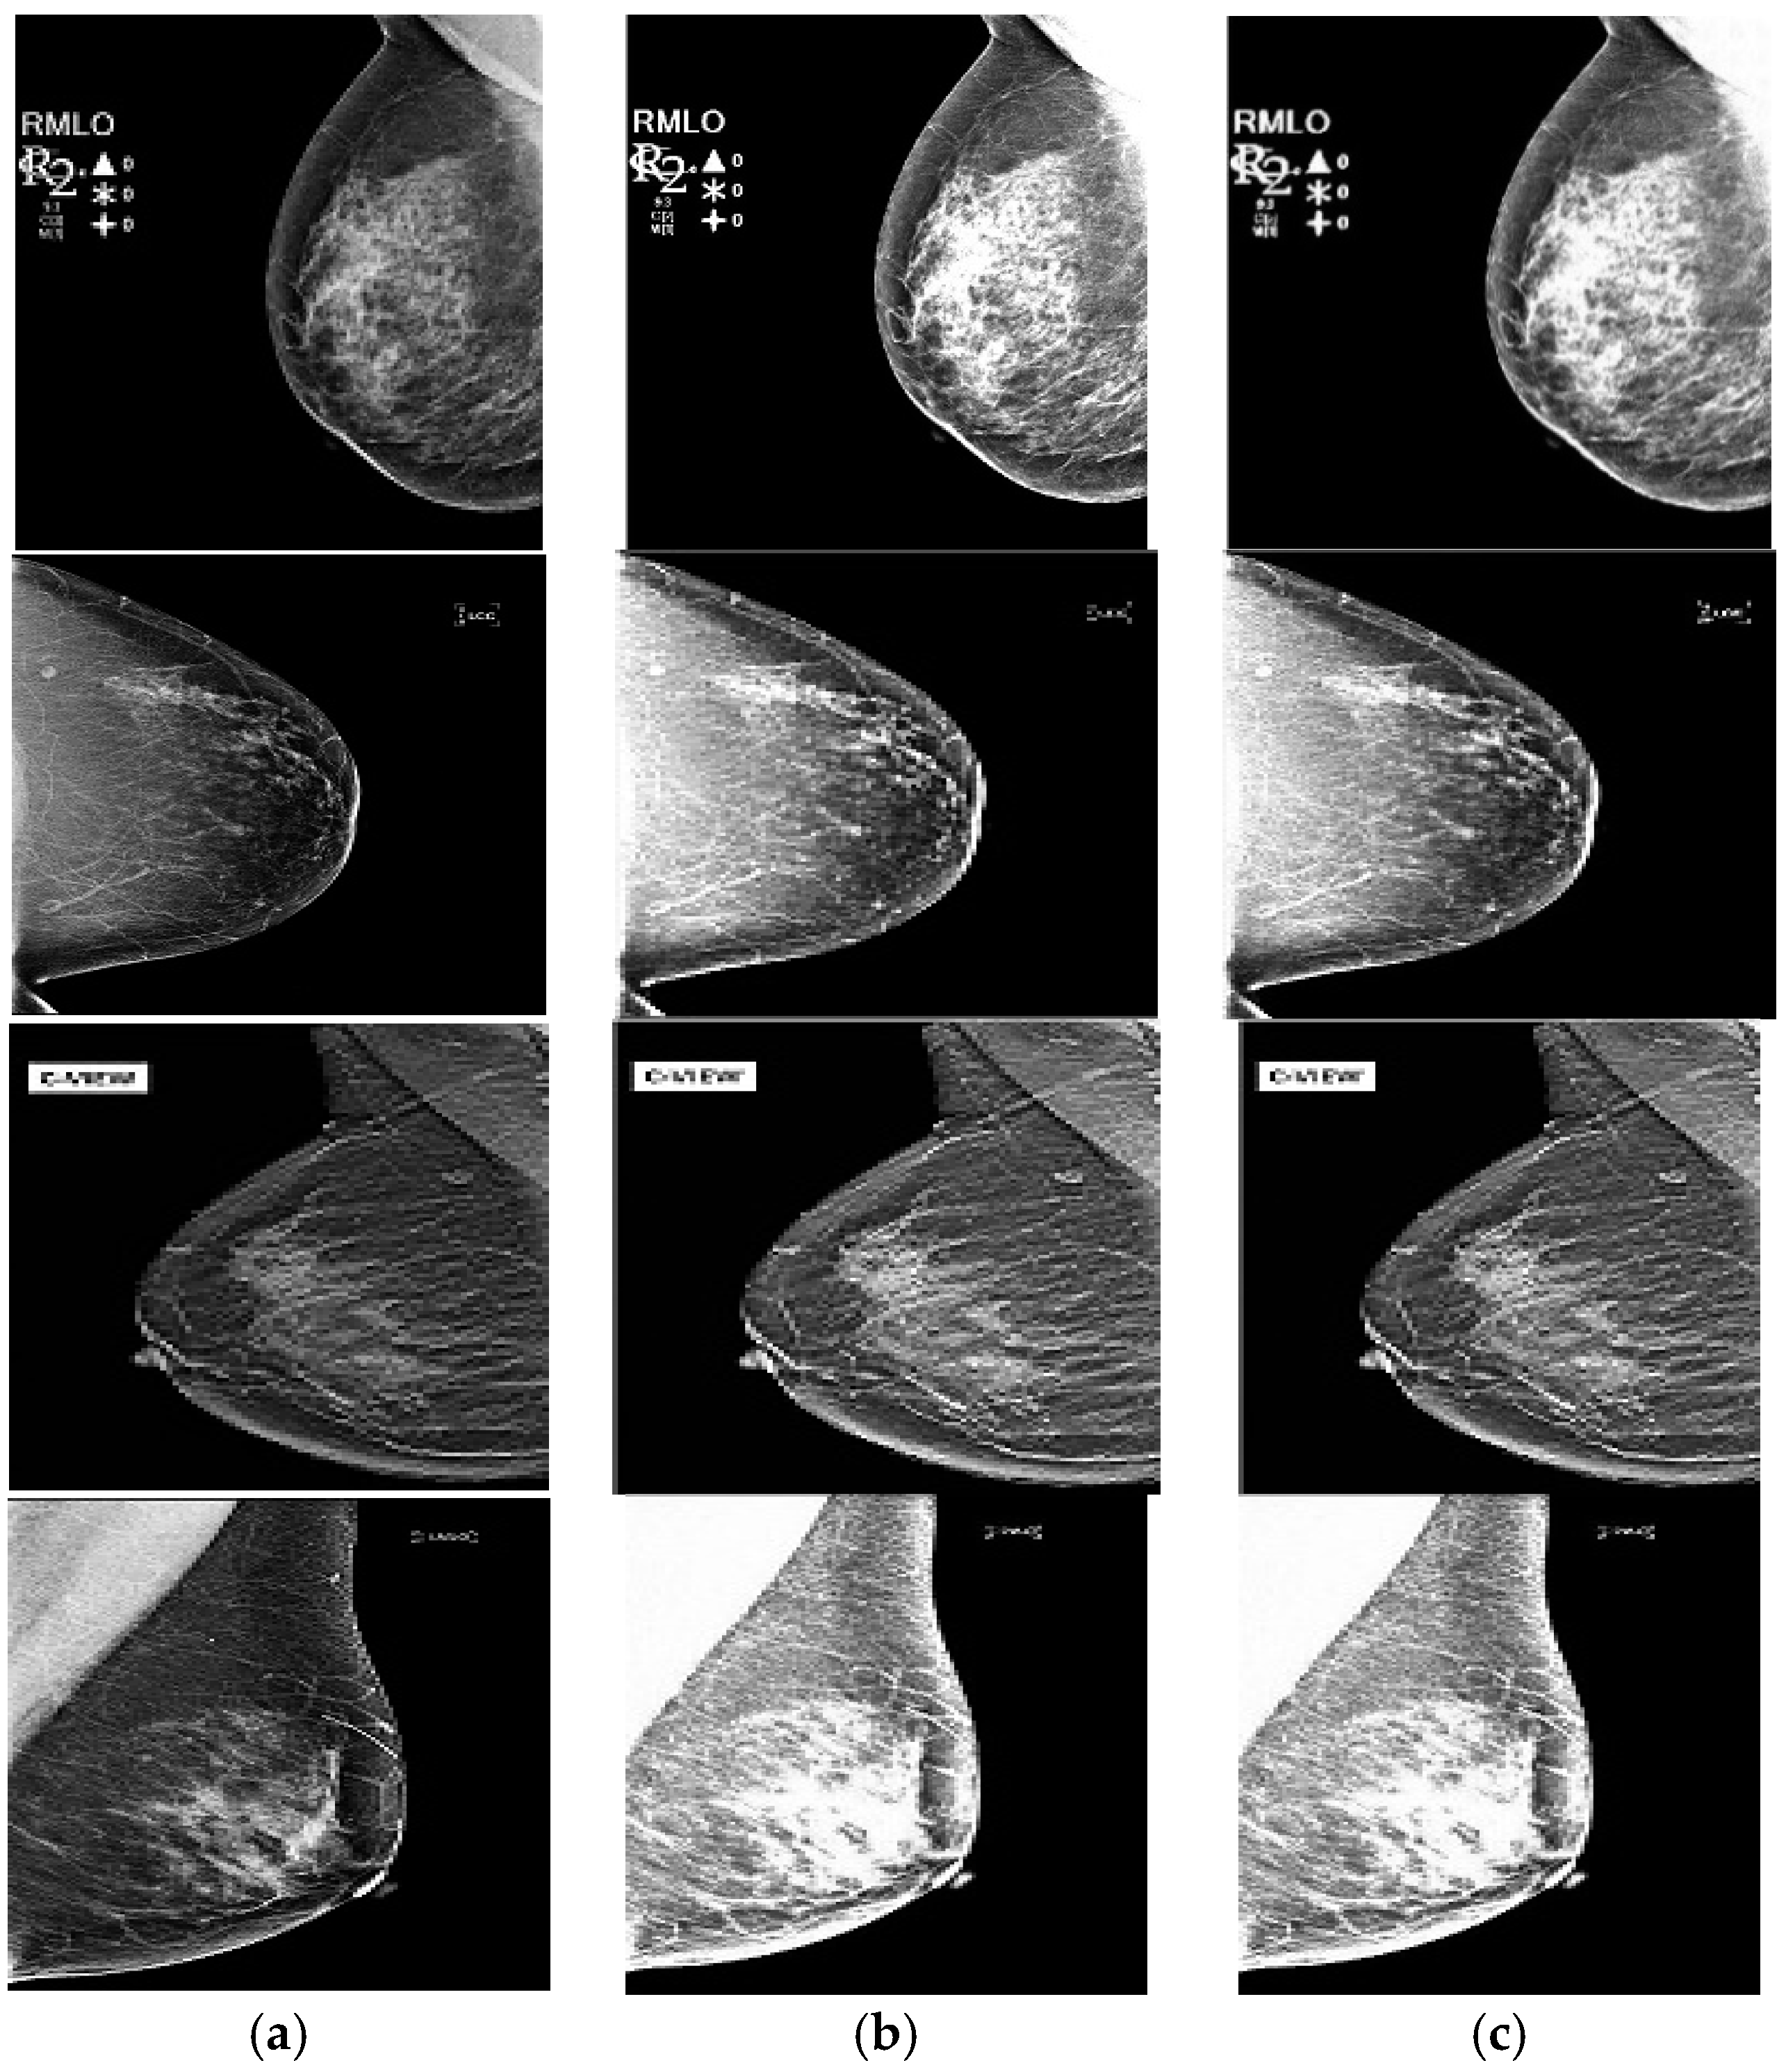

4.3. Enhancement Response of PSO-Optimized S-Curve Transformation

4.4. Fusion Response and Performance Measurements